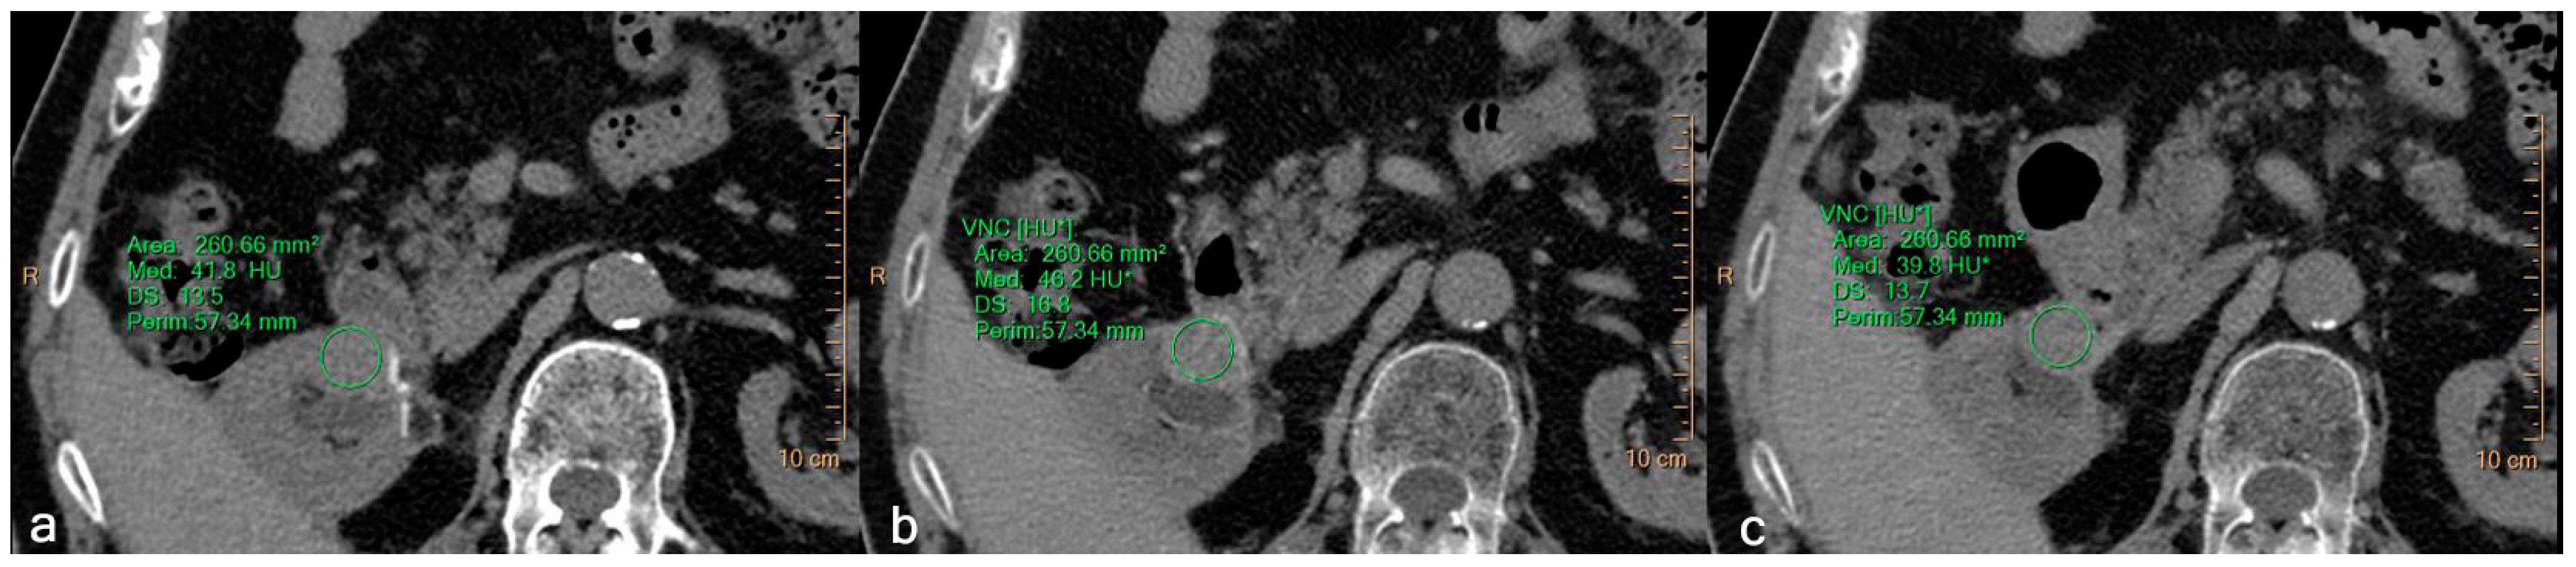

2.4. Objective Image Evaluation

3.2. Quantitative Assessment

| Type of Lesion | Phase | Mean Value (HU) | SD |

|---|---|---|---|

| All lesions | TNC | 17.6 | 16.5 |

| VNCcort | 15.7 | 13.2 | |

| VNCneph | 15.6 | 12.7 | |

| Simple Cysts | TNC | 10.7 | 15.6 |

| VNCcort | 7.8 | 12.2 | |

| VNCneph | 7.5 | 11.9 | |

| Complex Cysts | TNC | 15.3 | 18.6 |

| VNCcort | 12.7 | 13.6 | |

| VNCneph | 13.1 | 14.4 | |

| Renal Masses | TNC | 34.3 | 16.9 |

| VNCcort | 34.1 | 15.1 | |

| VNCneph | 33.9 | 13.4 |